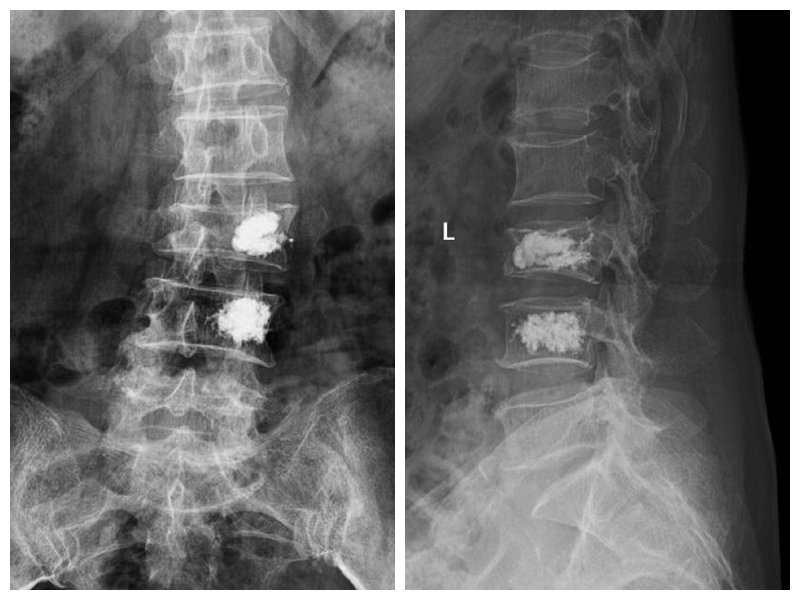

经皮椎体成形术及球囊复位、椎体后凸成形术

经皮椎体成形术及球囊复位、椎体后凸成形术适用于老年性骨质疏松性椎体压缩骨折及肿瘤性病理性压缩骨折。手术创伤小,术后疼痛缓解迅速、恢复时间短,疗效可靠。使患者及早下床活动,改善患者的生活质量,减轻患者家庭及社会的负担。

典型病例:患者刘**,女,70岁,因“在家滑倒摔伤腰背部疼痛活动受限2天”步行入院。查体:腰3、4棘突压痛,椎体及椎旁压痛明显,双下肢肌力、感觉正常。

术后第1天患者下地行走,腰痛明显缓解。(骨科二区 孙进)